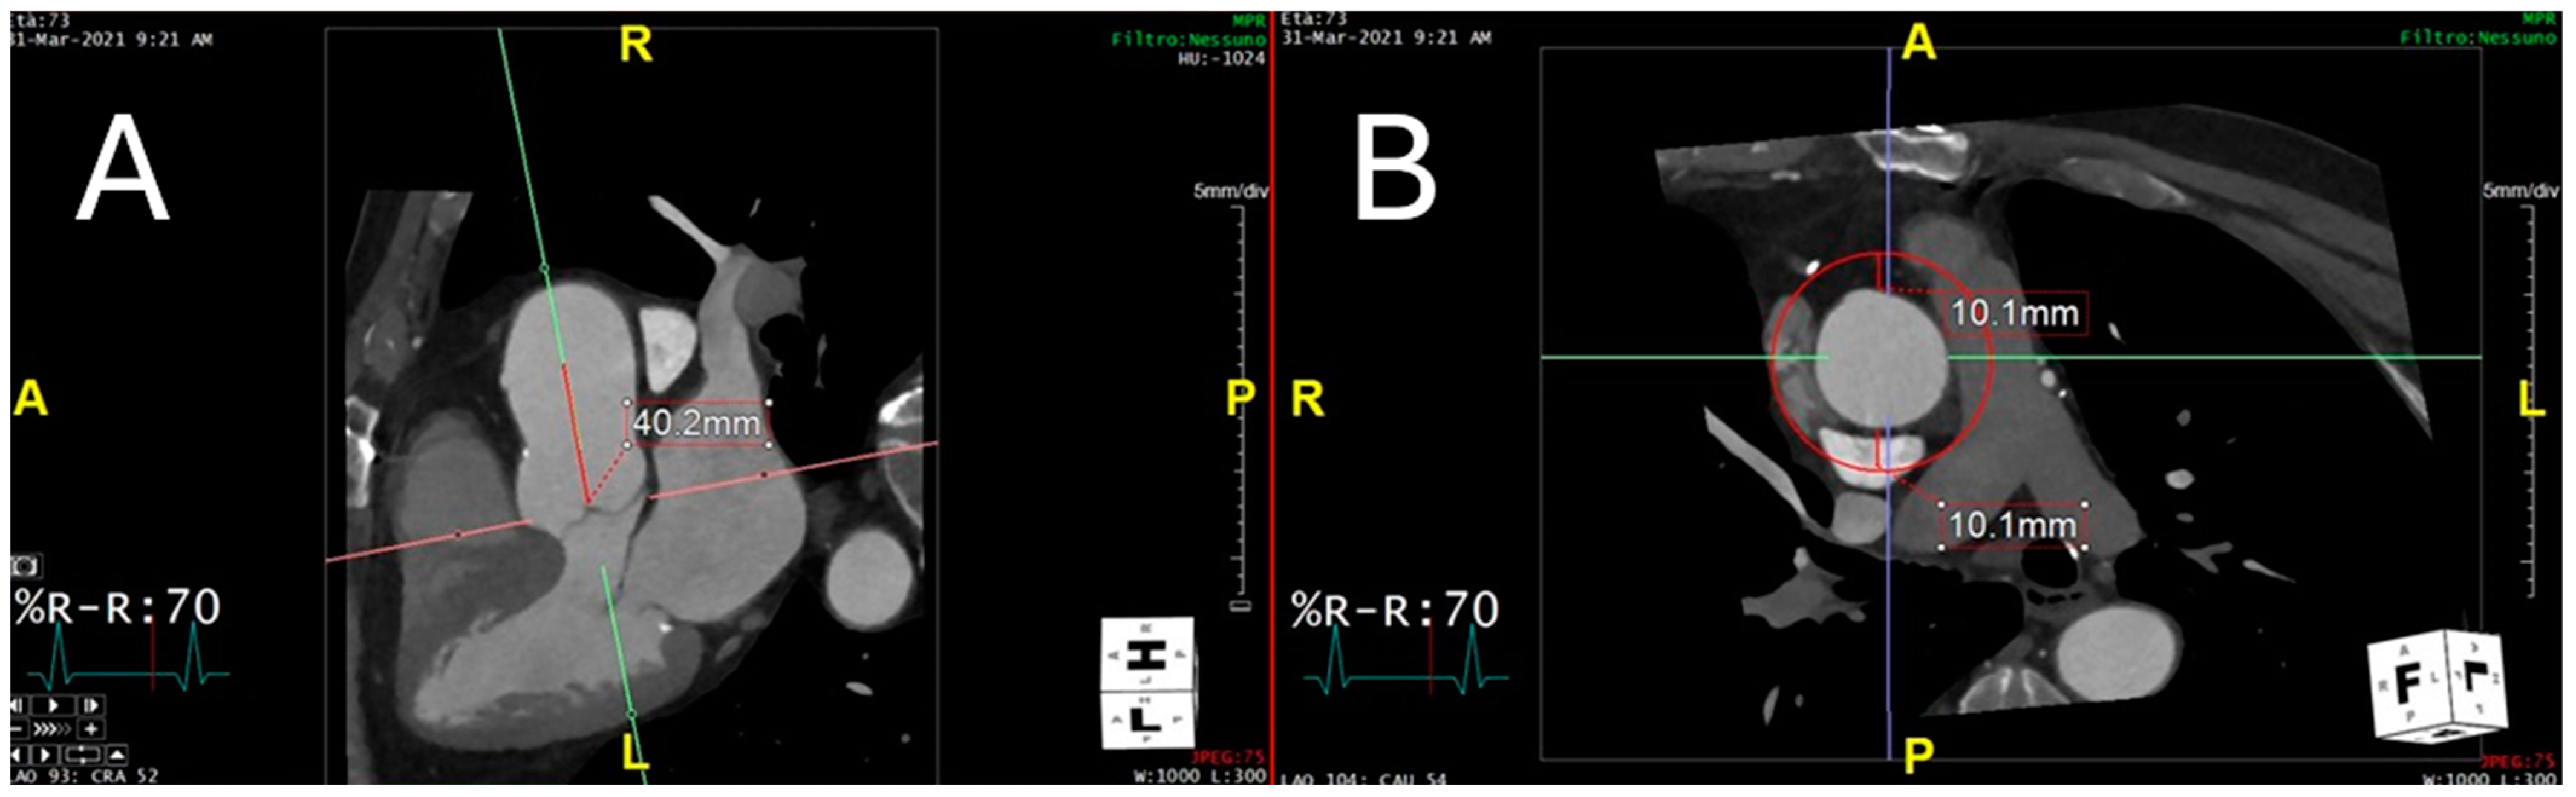

2.4. Technical Steps Required to Measure Perivascular Adipose Tissue Attenuation of the Proximal Ascending Thoracic Aorta on Chest Computed Tomography Angiograms